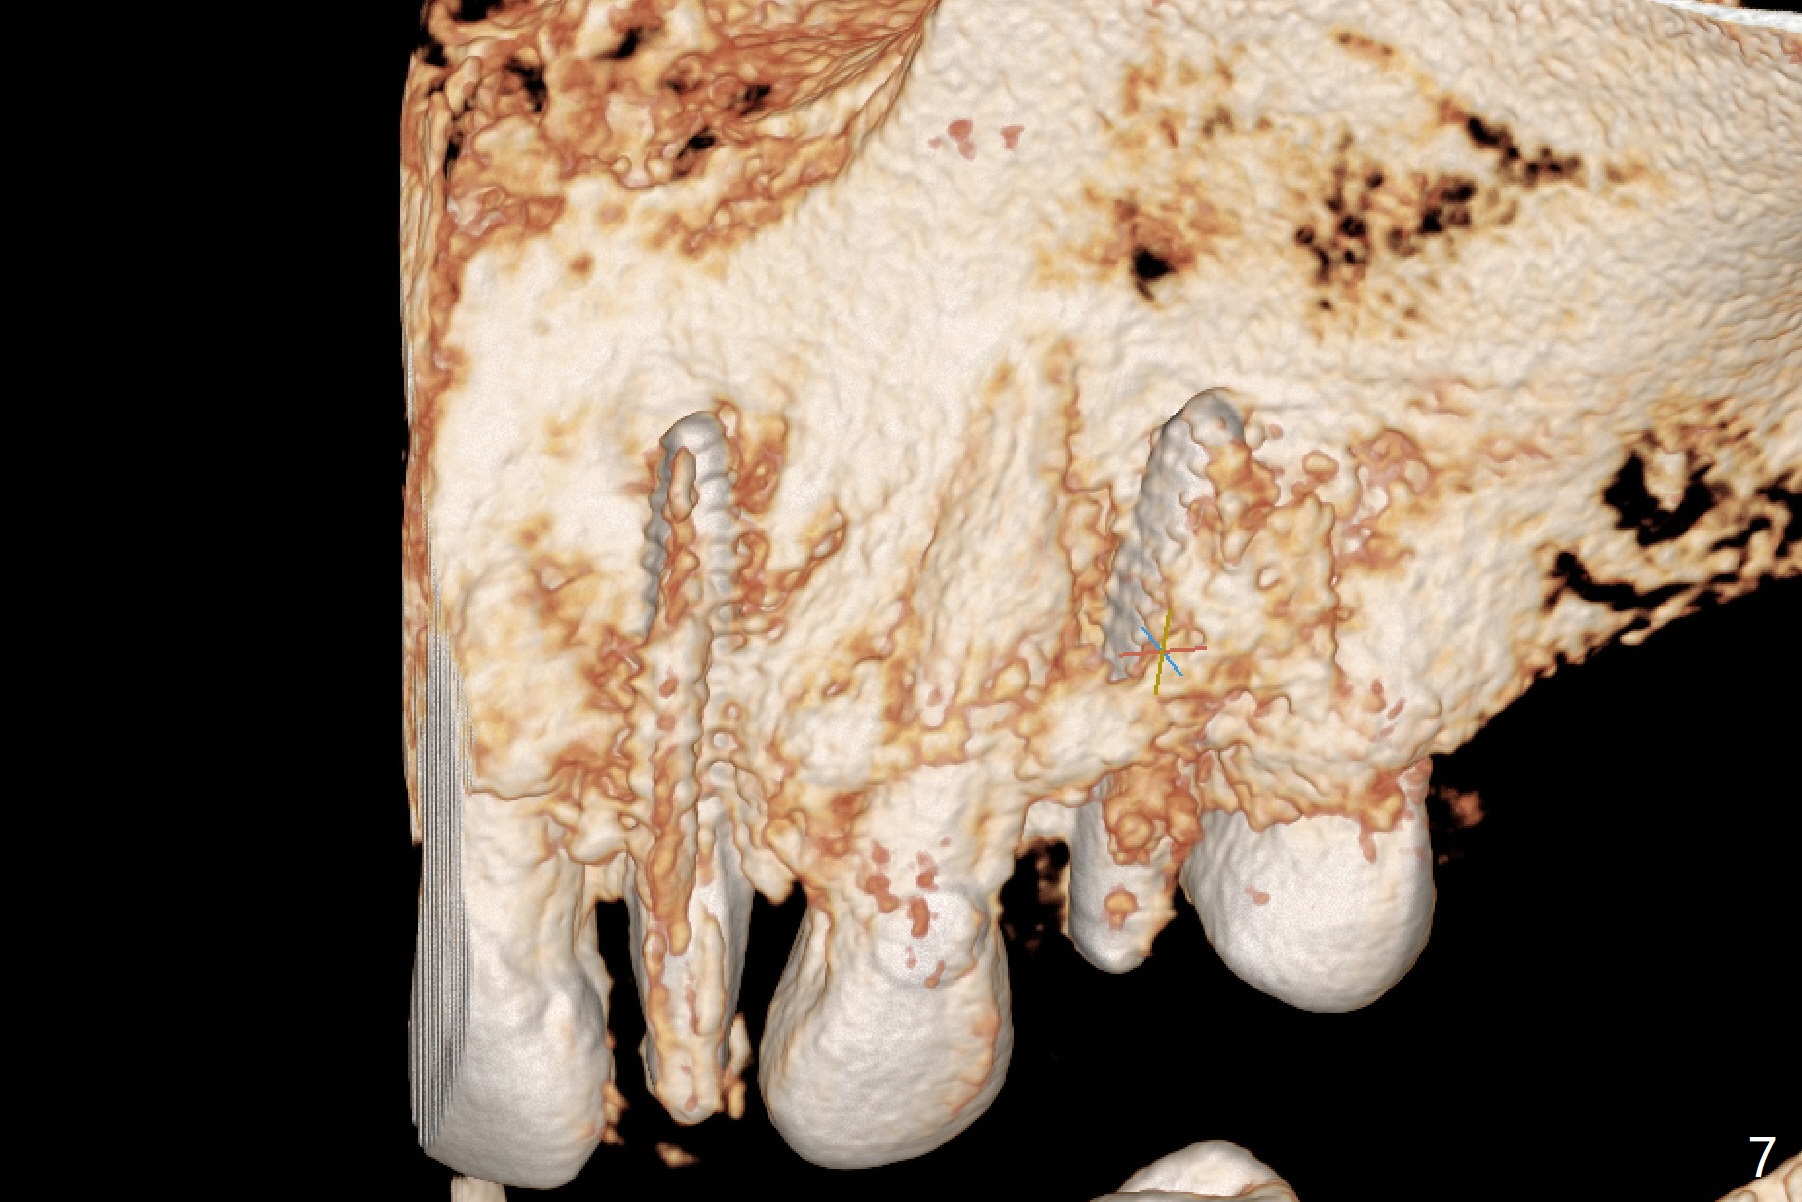

After removal of #10 sleeve and 3 spot adjustment, the guide is seated without satisfaction. When the guide is removed after pointed drill, the osteotomy seems distal (Fig.1). Incision is made with flap elevation for free hand osteotomy. A 1/1.6 mm bone expander is inserted after 1.2 mm drill, the trajectory appears to be right (Fig.2). As the osteotomy increases in diameter, the buccal plate feels to be vibratory. A 3.5x11.5 mm 1-piece implant placed initially is apparently away the sinus floor (Fig.3). Further placement (subcrestal, Fig.4) seems to be associated with more buccal plate perforation (Fig.6 *), which is repaired by bone graft. Since the implant at #10 appears to be doing okay 1.5 months postop (Fig.5), the implant at #12 is not removed immediately. A tunnel incision will be made for bone graft in the most apical concave areas (Fig.7). The osteotomy should have been made more palatal to reduce the chance of the buccal perforation. CBCT should have been taken while the 1/1.6 bone expander was in place.